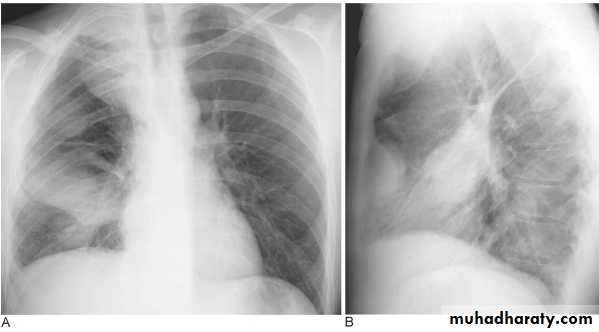

Pleural Effusion on Chest Radiographs.

Posteroanterior (A) and lateral (B) chest radiographs demonstrate the typical meniscoid appearance (arrows) in a patient with a left pleural effusionHydropneumothorax.

(A) PA and (B) lateral chest radiographs. Pleural fluid is encapsulated in the major fissure and against the anterior chest wall. These encysted fluid collections can mimic a lung tumour.Empyema.